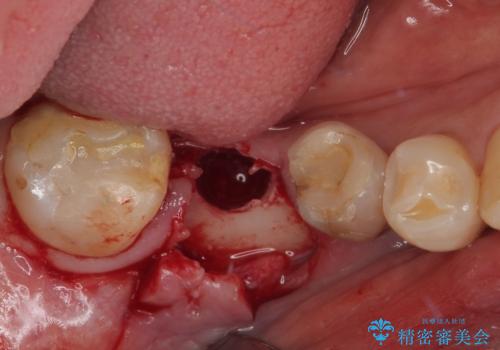

インプラント埋入時に植立具合の安定性を測定したところ、十分な数値が得られたため、速やかに仮歯を装着して咬合回復をさせることができました。

外科処置を1回に抑えることができ、あっという間に治療を終えることができました。